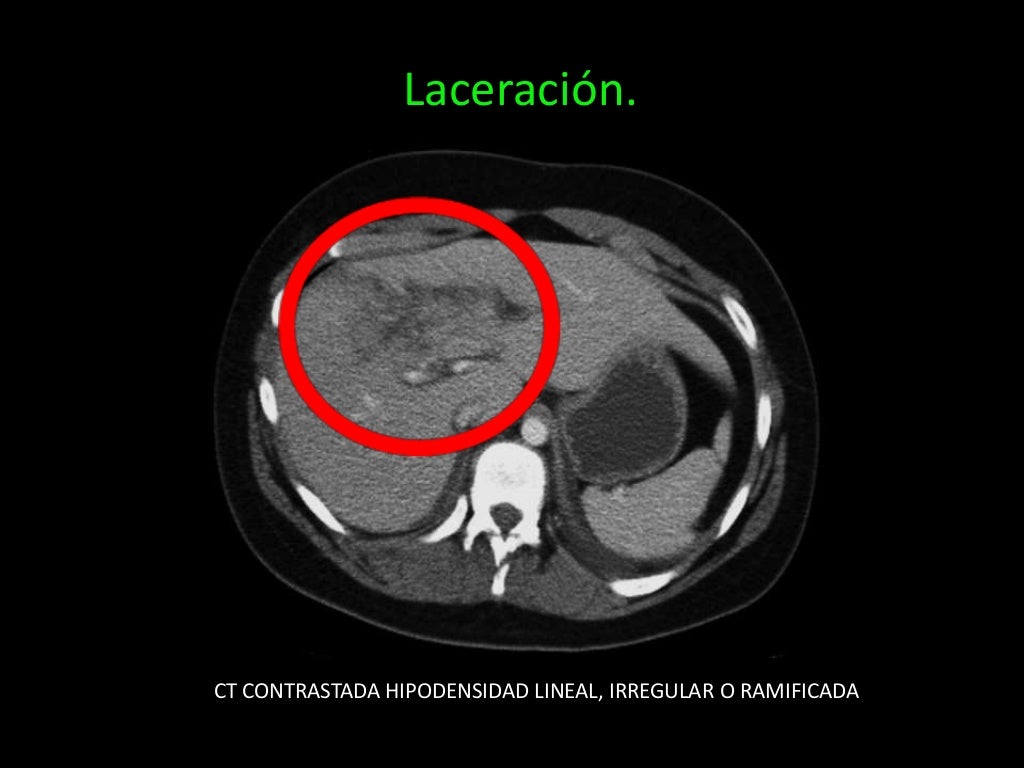

Tomografía abdominal que muestra zona de licuefacción y edema en la

Tomografía Axial Computarizada (TAC) del abdomen que muestra una